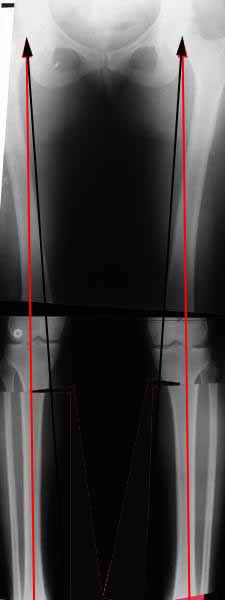

Мне представляется оптимальным на уровне 3-4 линии (т.е. как раз посредине отмеченной зоны). Если рассчимтываешь делать медиализацию, то параллельно суставной поверхности, иначе просто не сдвинешь без джистракции - отломки зацепятся. Если без медиализации - то вообще не имеет значения.